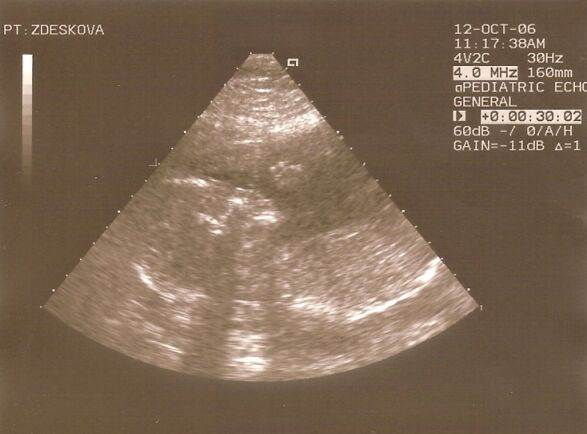

Marcelka Blažejovská a Martin Zdešek

Svatba dopadla nad očekávání výtečně! Počasí vyšlo krásné, přijela se na nás podívat spousta přátel, každý měl dobrou náladu, nikdo se nepohádal a všichni se skvěle bavili. Asi měsíc po svatbě jsme zjistili, že čekáme miminko. Tak jsme založili nov…